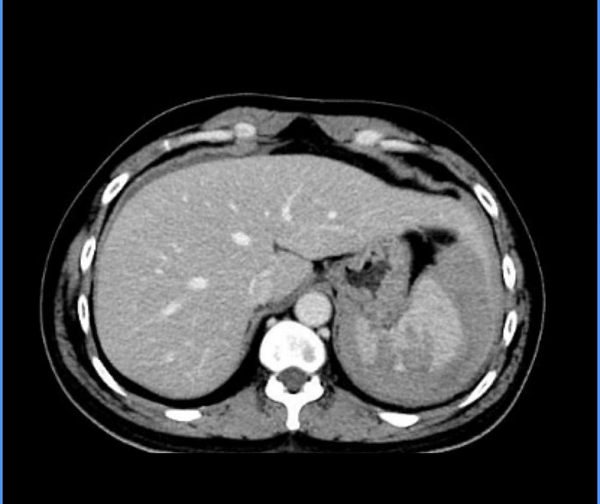

2. 全脾切除术+自体脾移植术:针对一名车祸致脾破裂的急危重症患者,郭陵副主任医师、邓彬副主任医师、刘健医师、汤如波医师团队第一时间启动急诊绿色通道,争分夺秒开展手术。术中清理腹腔积血及凝血块约2500ml,手术团队操作高效、配合默契,全程把控手术安全,顺利完成全脾切除术+自体脾移植术。术后患者生命体征平稳,各项指标逐步恢复正常,充分展现了我院肝胆血管外科在急危重症外伤救治中的硬核实力与应急处置能力。